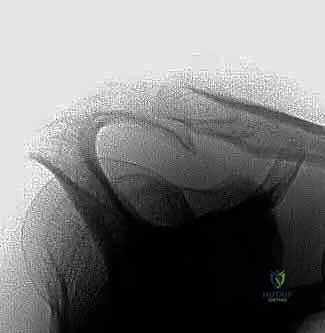

أشكال عظم الأخرم (تصنيف بيجلياني Bigliani)

يلعب شكل عظم الأخرم دوراً حاسماً في احتمالية الإصابة بالانحشار. صنف الطبيب بيجلياني الأخرم إلى ثلاثة أشكال رئيسية بناءً على صور الأشعة السينية:

* النوع الأول (المسطح - Flat): مساحة واسعة تحت الأخرم، خطر ضئيل جداً للانحشار.

* النوع الثاني (المنحني - Curved): انحناء طفيف لأسفل، يقلل المساحة، خطر متوسط للانحشار وتمزق الأوتار.

* النوع الثالث (المعقوف - Hooked): ينحني بشكل حاد لأسفل مثل الخطاف، يضيق المساحة بشدة، ويرتبط بشكل وثيق جداً (أكثر من 70%) بتمزقات الكفة المدورة وانحشار الكتف الشديد.

الهدف الأساسي من جراحة "تجميل الأخرم" (Acromioplasty) هو تحويل الأخرم من النوع الثاني أو الثالث المعقوف، إلى النوع الأول المسطح، لتوفير مساحة آمنة للأوتار.

* الأشعة السينية (X-rays): لتقييم شكل الأخرم (النوع 1، 2، 3) والبحث عن النتوءات العظمية أو التكلسات.